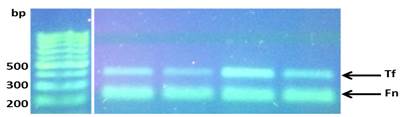

Se realizaron PCR con cada par de oligonucleótidos utilizando los genomas extraídos de la cepa silvestre. Los cebadores utilizados para la detección de las especies bacterianas A. actinomycetemcomitans, P. gingivalis, P. intermedia, T. forsythia y F. nucleatum fueron los que se muestran en la Tabla 1. Las condiciones de las PCR multiplex para la detección de estos microorganismos se muestran en las Tablas 2 y 3.

La visualización de los resultados de las amplificaciones (bandas) se realizaron en geles de agarosa al 1.2%, buffer TBE (Tris-borato-EDTA) 0.5x, 5µl de GoodView, 2µl de cyan/orangeloading buffer; 2-5 µl del producto del PCR durante 2h a 80V; y fotografiados con una cámara digital colocada encima de un transiluminador con luz ultravioleta (UV) (Figs. 4 y 5).